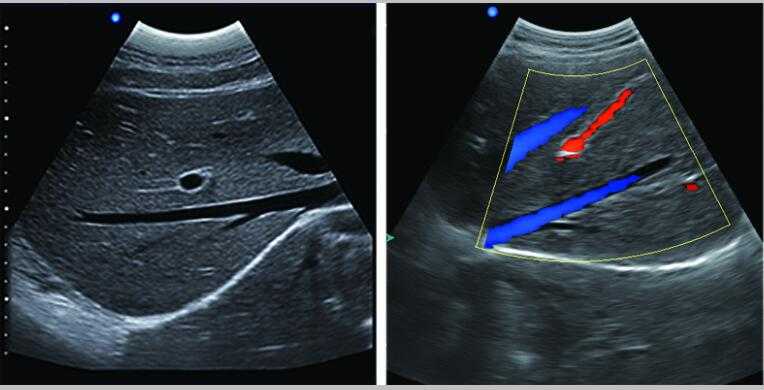

彩色多普勒

采用智能圖像處理技術1.組織諧波成像技術 2.噪聲抑制斑點技術 3.多波束并行處理技術等

7.應用:腹部、婦科、產科、心臟、血管和小器官、泌尿科、肌肉骨骼、兒科等